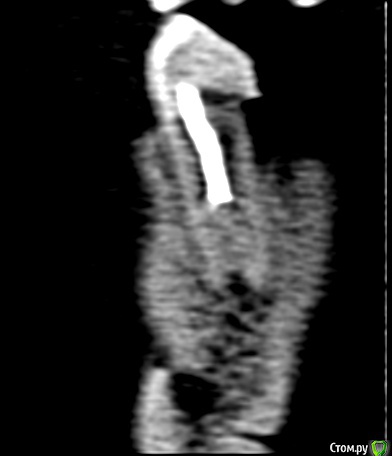

shurkne Опубликовано 1 мая, 2015 Поделиться Опубликовано 1 мая, 2015 (изменено) Здравствуйте!зуб 3.5Полтора года назад лечен резорцином(начал беспокоить...я как понимаю там периодонтитподскажите перелечивать его или удалять? Изменено 1 мая, 2015 пользователем shurkne Ссылка на комментарий

shurkne Опубликовано 13 мая, 2015 Автор Поделиться Опубликовано 13 мая, 2015 Начал перелечивать этот зуб!лечение проводилось под микроскопомврач смог пройти только 1 канал...второй смог пройти на половину(сказал все закаменело..можно перфорацию получить)в проходимый канал положили каласепт на 2 недели или больше Предложение дальнейшего лечениянепроходимый канал запломбировать чем то что замумифицирует каналв проходимый гутаперчу поделитесь вашими мнениями.... Ссылка на комментарий

shurkne Опубликовано 13 мая, 2015 Автор Поделиться Опубликовано 13 мая, 2015 Да он и не болел..... Просто на кт увидел периодонтит и решил довести зуб до ума.... А то потом бы заболел) Ссылка на комментарий